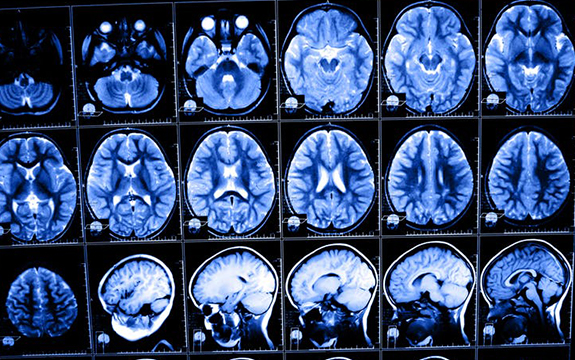

The brain is very complex and well-protected, which makes it difficult for researchers to measure its temperature. Shutterstock/Nata-Lia

The brain is not only extremely complex, it is also very delicate and well-protected. To make matters more complicated, brain temperature changes associated with significant variations in neural activity are usually small (below 1℃) and may occur very rapidly over a small area.